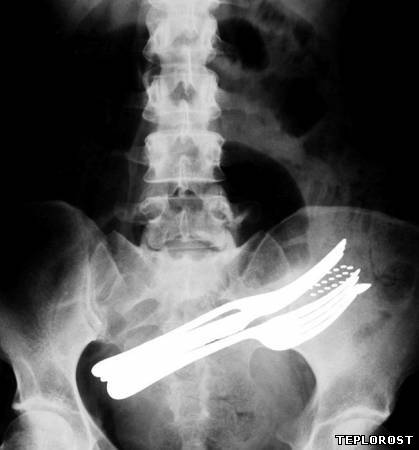

Этот пациент проглотил столовые пиборы